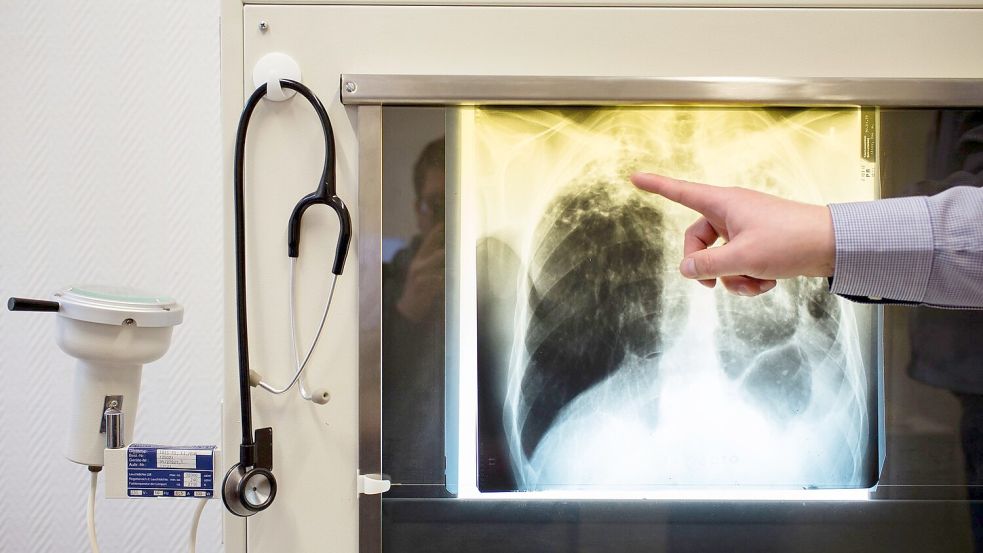

Tuberkulose wird unter anderem über die Luft übertragen. Zu den Symptomen zählt vor allem Husten, möglich sind zudem Brustschmerzen und Appetitverlust. Die Bakterien können neben der Lunge auch andere Organe befallen. Ohne Behandlung führt eine Tuberkulose‑Erkrankung laut WHO‑Daten bei etwa jedem zweiten Betroffenen zum Tod.